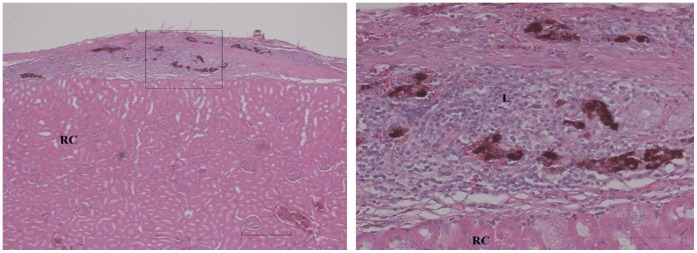

Figure 2. Survival of transplant in Zebularine treated rat at the end of the 90-days observation period.

Left: Insulin positive cells (red-brown) of the transplant (T) are seen superficial to the normal renal cortex (RC) (semiquantitative scoring of +++). A large collection of leucocytes (L) is buried deep into the transplanted tissue. Bar is 400 µm. Right: The area outlined in a higher magnification; insulin positive cells are easy to distinguish from adjacent leucocytes and renal parenchyma. Bar is 80 µm.

Rats normoglycemic for 90 days after allografting were subjected to transplant removal by nephrectomy to confirm whether euglycemia was indeed due to a surviving insulin producing transplant, or alternatively was a result of recovery of pancreatic insulin production (see above). A total of 7 rats (2 controls and 5 Zebularine treated) were normoglycemic at day 90 due to pancreatic recovery as demonstrated by failure of nephrectomy to induce hyperglycemia and these rats were excluded from further evaluation. Of the remaining 9 Zebularine treated rats, 4 were still euglycemic after 90 days and became hyperglycemic after nephrectomy (histological scoring +++ for three of them (see Figure 2) and ++ for one). The mean length of time the Zebularine group stayed normoglycemic was 67±8 (SEM) days after transplantation as compared to 14±3 (SEM) days for the 9 controls (Figure 3). This difference is highly significant (p<0.001, 2-sided Mann-Whitney). Median length of euglycemia was 84 days in the Zebularine treated group and 11 days in the control group. In the five Zebularine treated animals, which developed hyperglycemia before the end of the 90 days observation period was reached indicating rejection of the allograft, although delayed, there were remaining insulin expressing cells in 2 animals (histological scoring of ++ for both of them, diabetic at days 15 and 37) (Figure 4) but in 3 there were no such cells detectable (diabetic at days 51, 56 and 84).